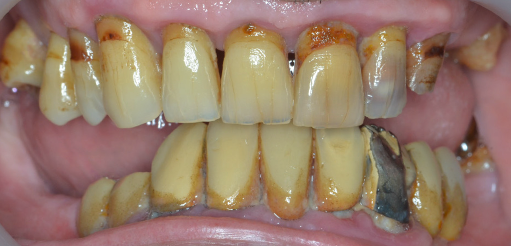

Lucrările pot fi realizate, în funcție de caz, pe ambele maxilare sau doar pe unul dintre maxilare. Atunci când pacientul prezintă lucrări vechi necorespunzătoare, sprijinite pe dinți care prezintă mobilitate crescută, (Fig. 3.6.1 lucrarea anterioară, mandibulară și Fig. 3.6.2) pacientul va rămâne edentat (fără dinți) în urma extracțiilor dinților mobili. În cazul acestui pacient, toți dinții superiori prezintă rectracții ale gingiei, iar cei din partea stângă (incisivul central, incisivul lateral și caninul) au fost tratați endodontic (tratamente de canal). Acest lucru a indicat acoperirea lor cu coroane metalo-ceramice (Fig. 3.6.3).